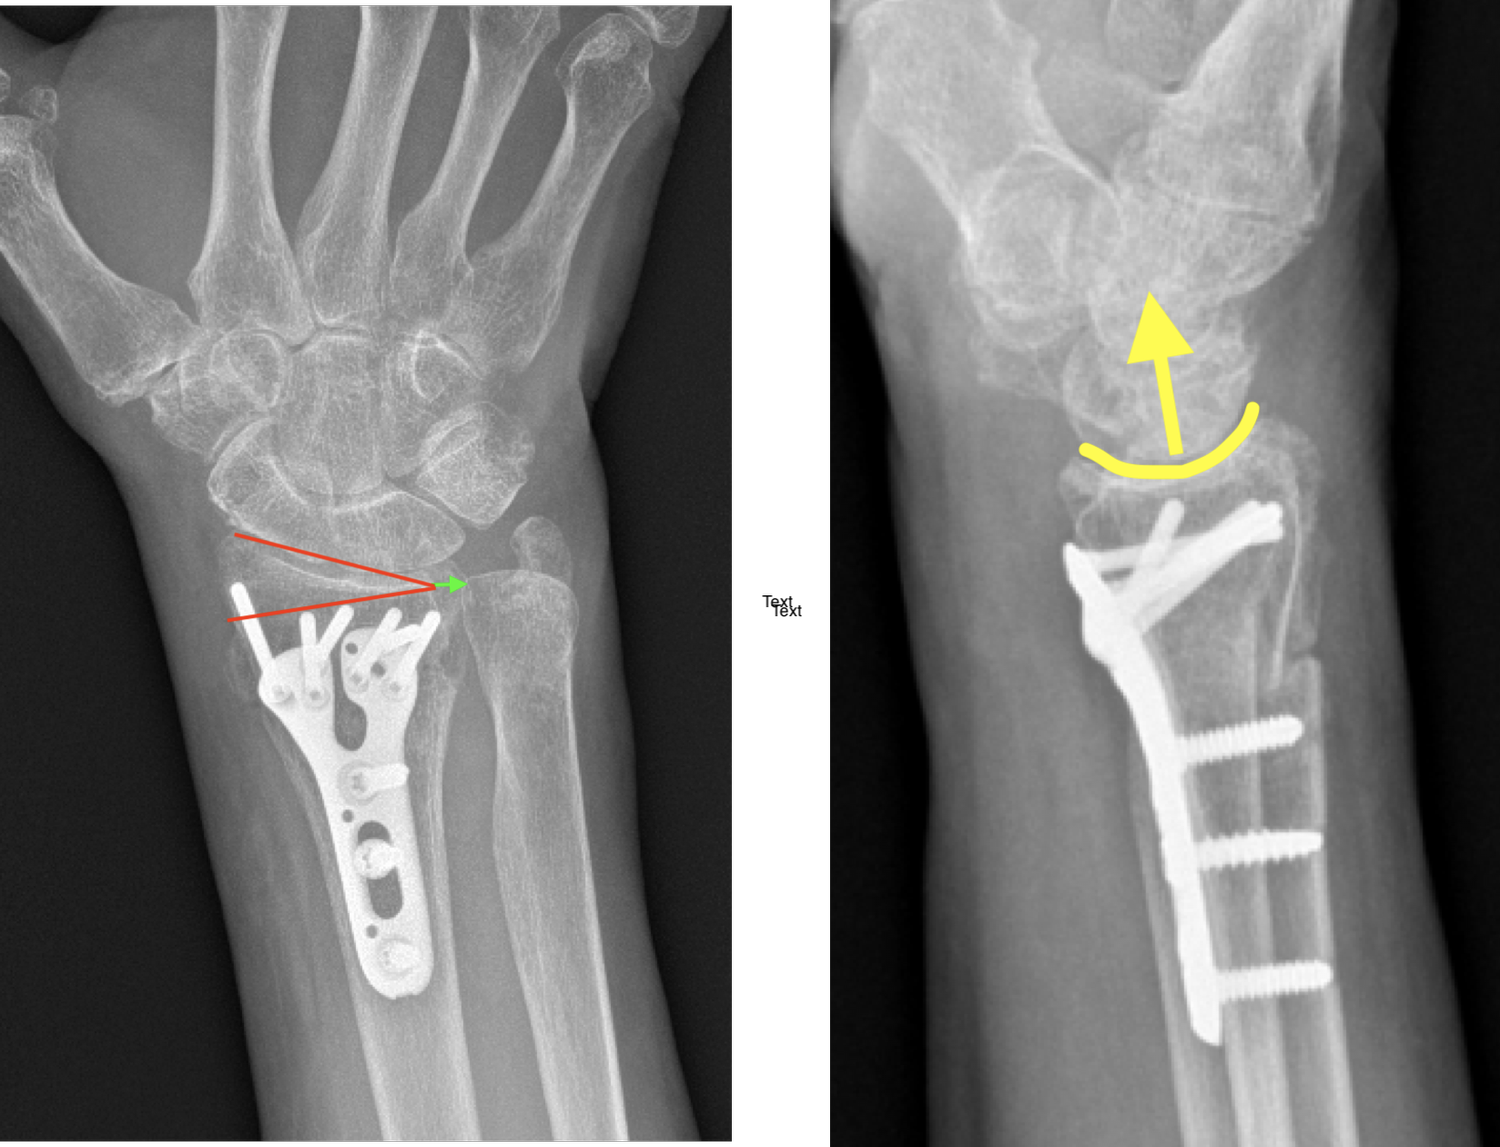

Figure 2 from Treatment of distal radius fractures with percutaneous

Figure 2 from Treatment of distal radius fractures with percutaneous How Long Does A Distal Radius Take To Heal It usually takes about six weeks for this type of fracture to heal. How long might it take for my distal radius fracture to heal? What is a distal radius. It usually takes around six to eight weeks for a fracture to heal. This injury can be treated in a removable cast or wrist splint for 5 weeks, this will. How Long Does A Distal Radius Take To Heal.